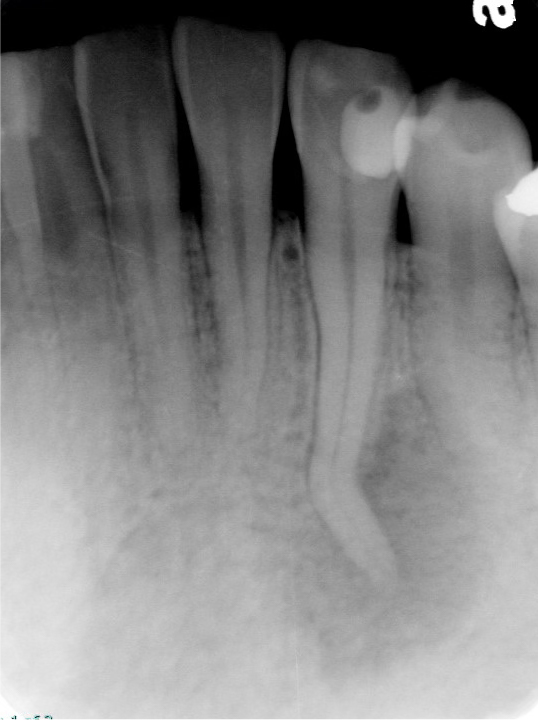

正放線投影(正面からまっすぐ)

根管治療の症例

偏遠心投影(後ろ(奥側)からナナメに)

2週間ほどズキズキした痛みが続き、温かいものがしみる症状がありました。かかりつけでは「抜髄が必要かもしれない」として紹介となりましたが、歯内療法の専門的な検査で感染や根の病気の可能性を丁寧に確認したところ、抜髄を急ぐ所見が乏しい状態でした。いったん経過観察とし、1週間後に痛みが消失。再評価でも所見は変わらなかったため、抜髄は行わず、修復物の調整・やり替え対応で終了しました。

年齢性別 40代・女性

主訴 2週間前からズキズキ痛む/温かいものがしみる

治療部位 左上7番

治療内容 診査・診断 → 経過観察 → 再評価 → 抜髄は行わず、修復物のやり替え依頼

治療回数 検査回数2回

リスク副作用 検査や経過観察の間に症状が再燃する可能性があります。必要に応じて追加検査や治療方針の変更が必要になる場合があります。